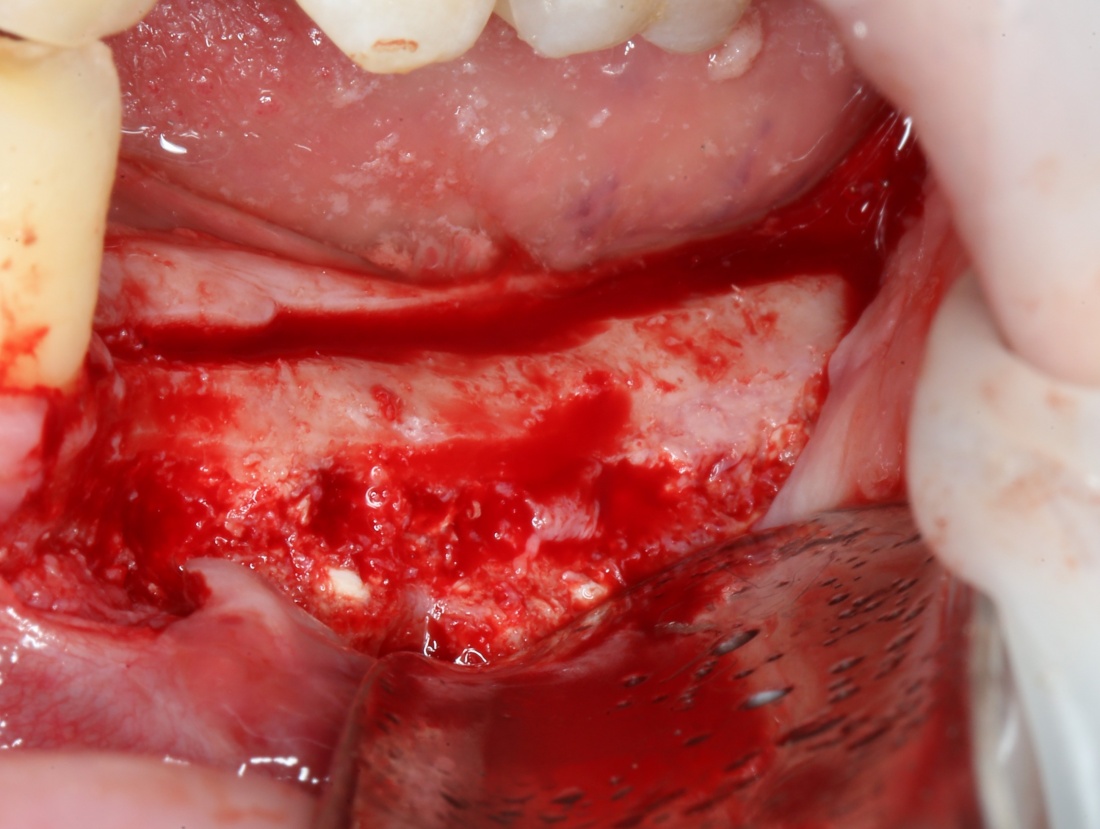

Кстати, обрати внимание на ширину альвеолярного гребня (левая картинка). Она чуть меньше 3 мм. Это объясняет, почему я засомневался в возможности установки имплантатов одновременно с остеопластикой. Понятно и без КЛКТ.

Наперво, мне нужно удалить разрушенный зуб и получить костный аутотрансплантат.

Для получения костного блока, мы открываем донорскую зону, наружную косую линию нижней челюсти.

Возвращаемся к основной операционной области. Еще раз посмотрим на альвеолярный гребень, поофигеваем от его ширины и моих грандиозных планов: